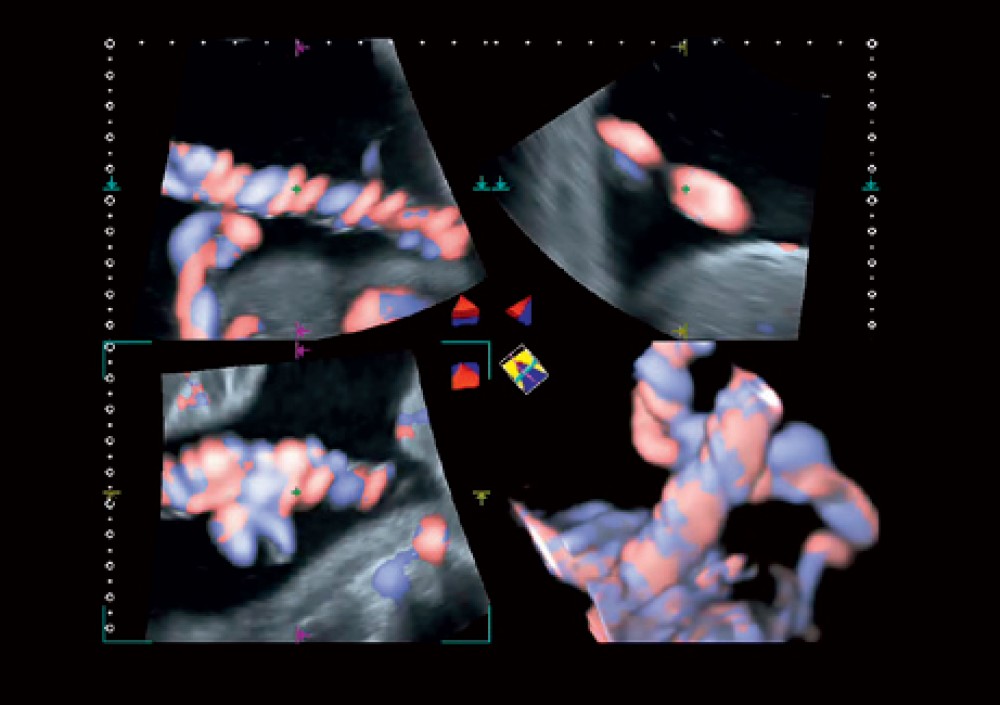

Advanced Dynamic Flow™ (ADF): Qan axınının yüksək ayırdetməli rəngli görüntüləməsini təmin edir.

3D/4D görüntüləmə: Həcmi görüntüləmə ilə anatomik strukturların daha detallı qiymətləndirilməsinə imkan verir.